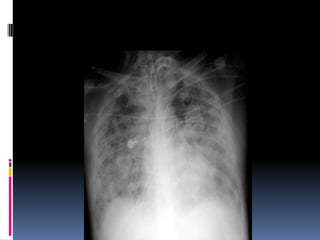

Lung fields

   Infiltrates

   Increased interstitial markings

   Masses

   Absence of normal margins

   Air bronchograms

   Increased vascularity

Cannon ball appearance- DDS

Osteogenic sarcoma

Thyroid (follicular)

Testicular carcinoma

Kidney

Choriocarcinoma

Prostate

Malignant melanoma,       Some GI,    Some very

advanced      nasopharyngeal, and    pharyngeal

carcinomas

Breast

Lymphangitis carcinomatosa

Lung fields  Infiltrates  Increased interstitial markings  Masses  Absence of normal margins  Air bronchograms  Increased vascularity

Cannon ball appearance-DDS Osteogenic sarcoma Thyroid (follicular) Testicular carcinoma Kidney Choriocarcinoma Prostate Malignant melanoma, Some GI, Some very advanced nasopharyngeal, and pharyngeal carcinomas Breast Lymphangitis carcinomatosa